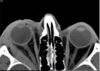

Pseudotumor Espessamento do músculo e tendão

A